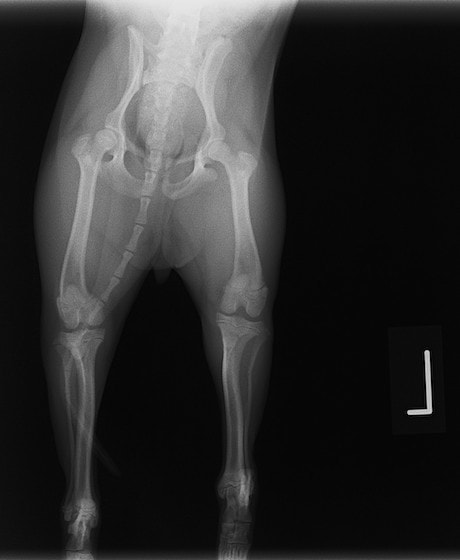

術後レントゲン